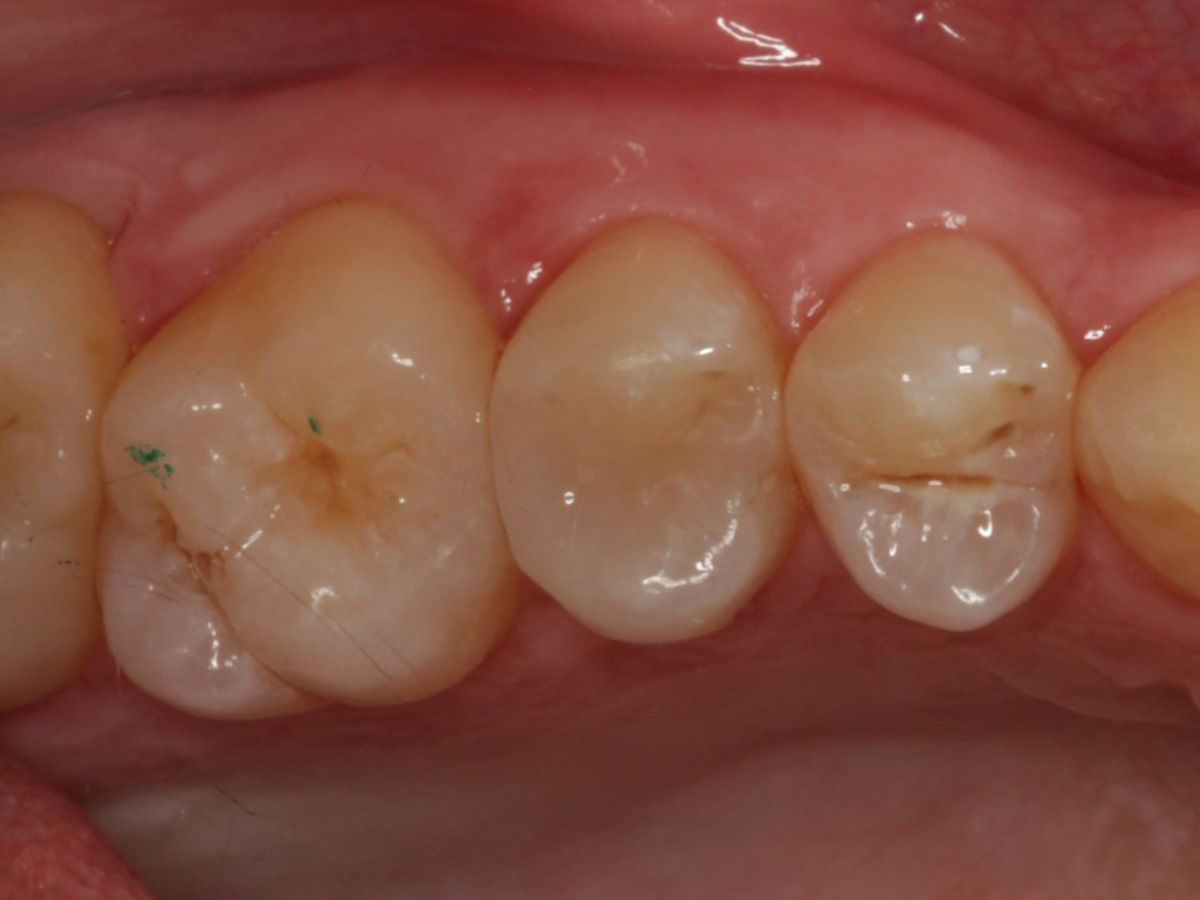

Abbildung 3

Quadrantenisolierung mit Kofferdam (x-heavy)